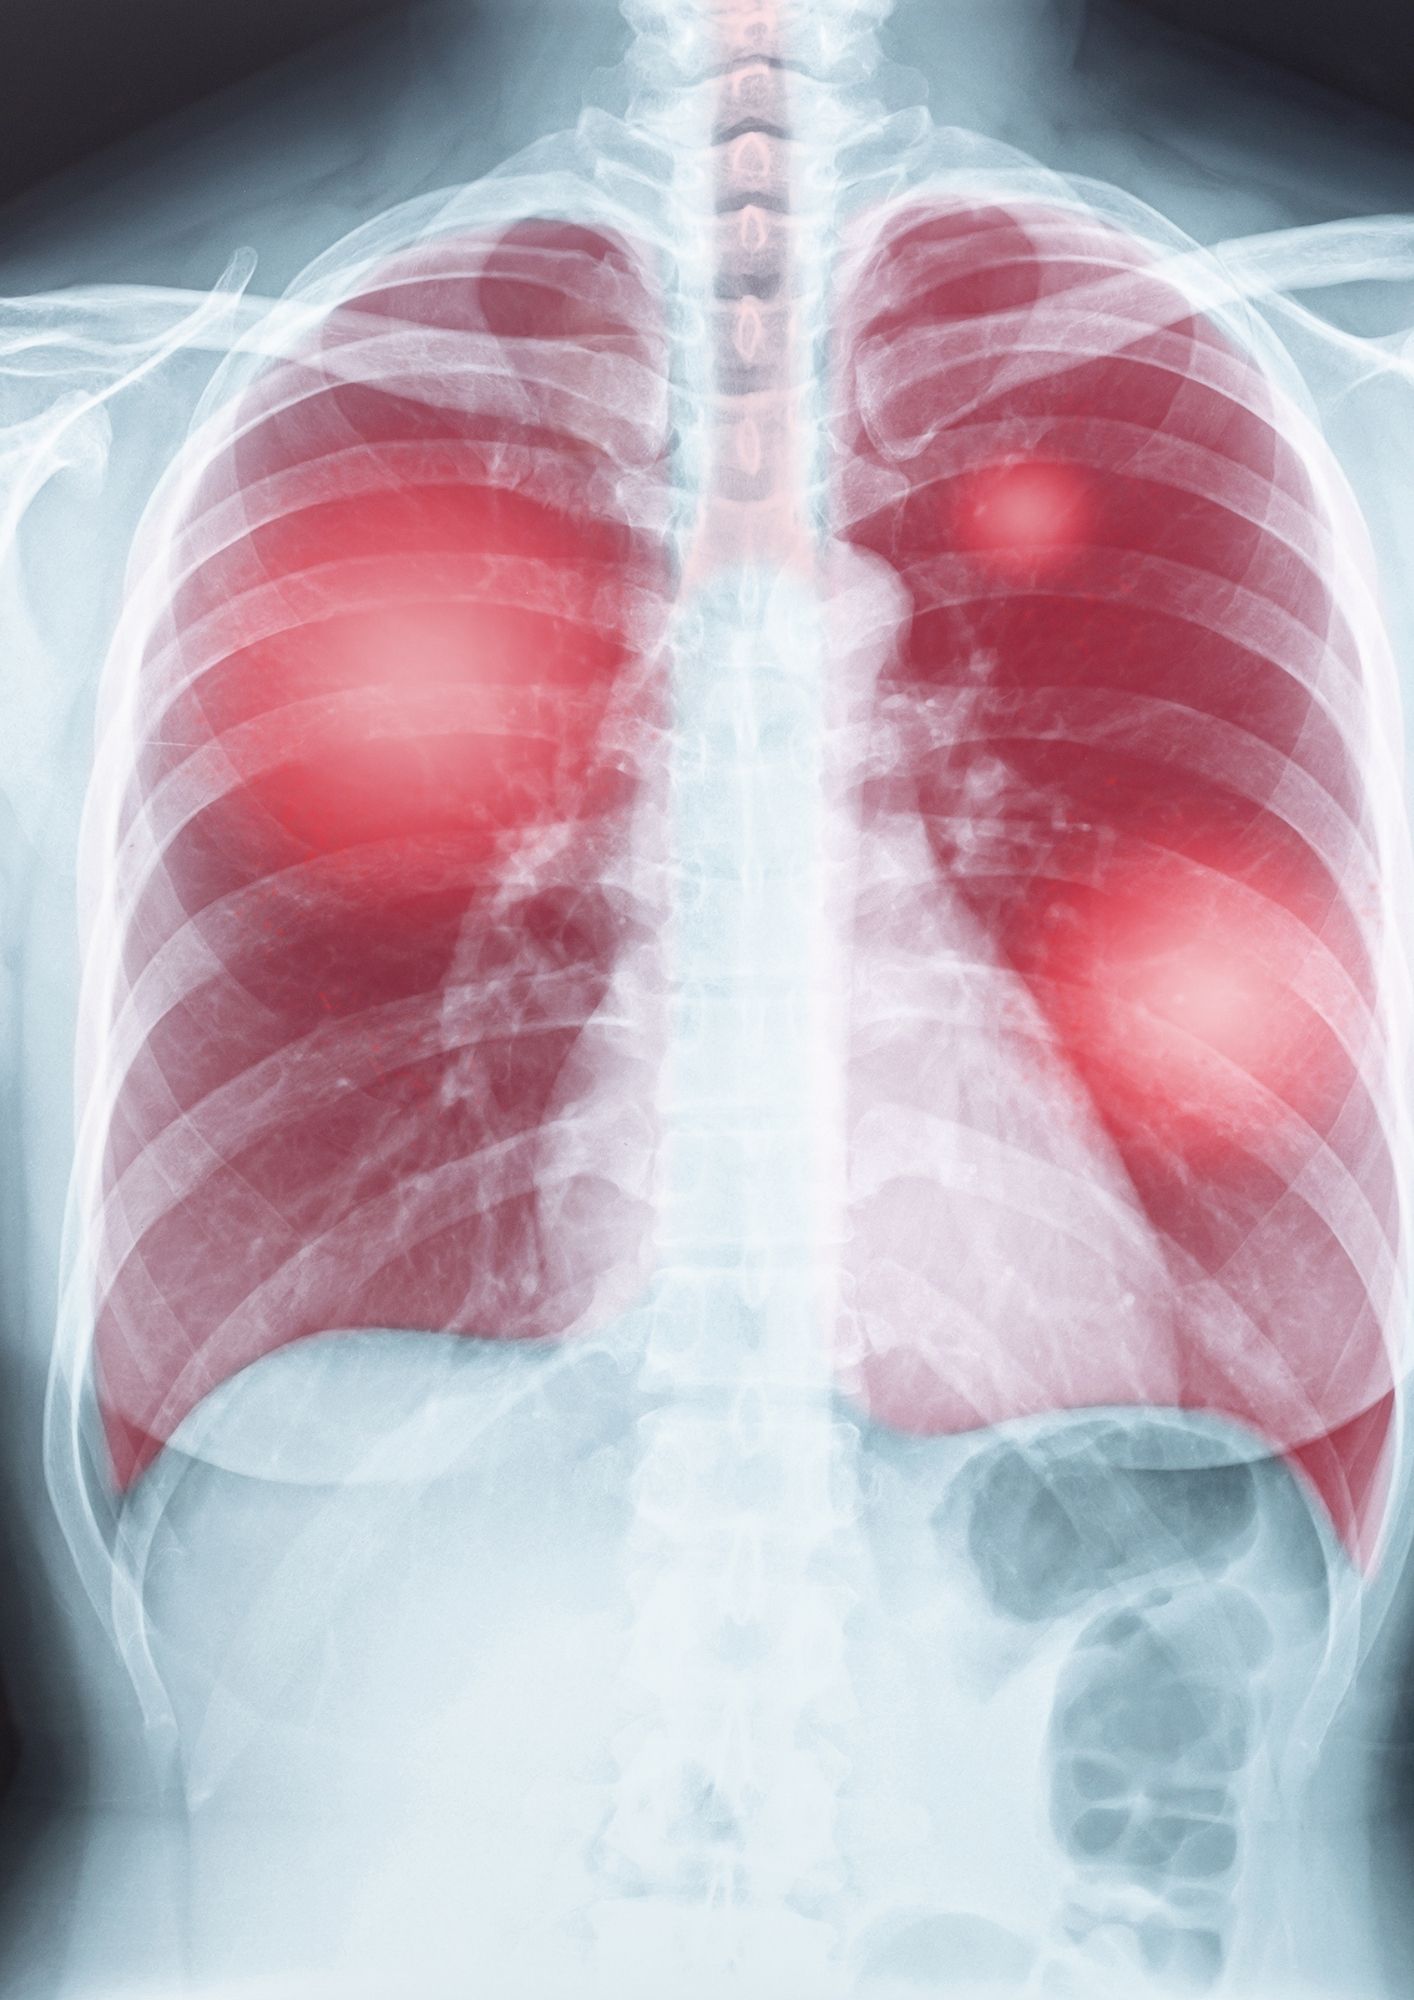

En 1895, Wilhelm Röntgen découvre les rayons-X qui deviennent quasi immédiatement l’outil de base de la détection de la tuberculose.